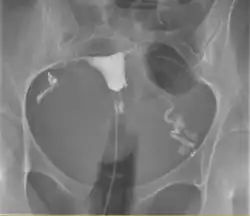

Histerosalpingografia, HSG – badanie rentgenowskie mające na celu uwidocznienie jamy macicy i jajowodów.

Technika ta pozwala diagnozować nieprawidłowości budowy macicy i jajowodów. Jest to badanie pierwszego rzutu w diagnostyce niedrożności jajowodów, mogącej być przyczyną niepłodności – jednak nie da się za jego pomocą wykryć endometriozy ani zrostów okołoprzydatkowych, które również mogą powodować niepłodność.

Odmianą histerosalpingografii jest histerografia, która jest ograniczona jedynie do obrazowania jamy macicy, polegająca na wprowadzeniu do niej środka cieniującego za pomocą specjalnej strzykawki. Podczas podawania środek kontrastowy stopniowo wypełnia jamę macicy, jajowód i następnie dostaje się do jamy otrzewnej.